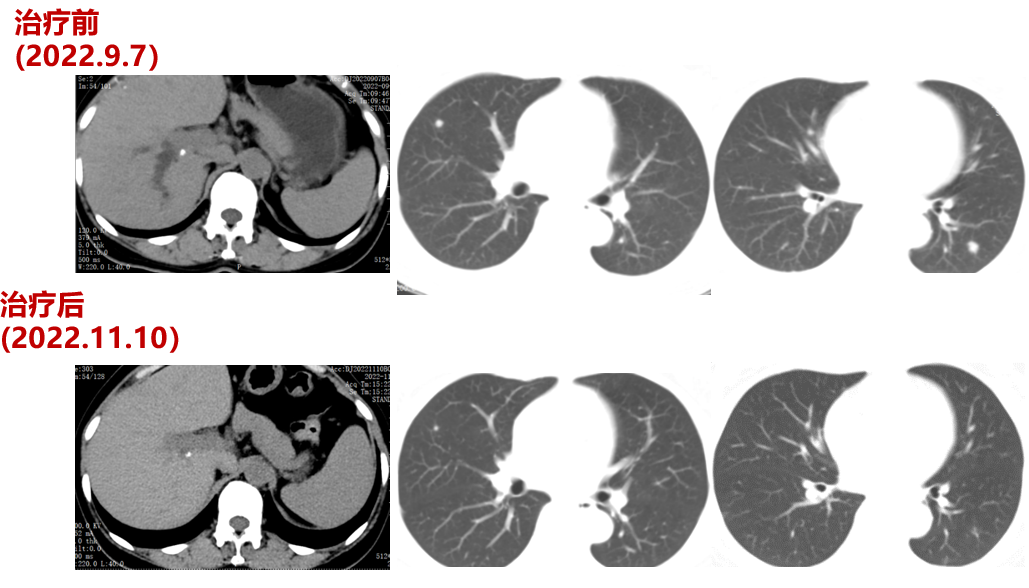

三线治疗(2022-9-7至2023-03-18,PFS:6月余):

2022-09-07至2023-01-03院外使用DS-8201治疗5周期。2周期后疗效评价:PR。CT示:腹膜后淋巴结较前部分缩小;双肺多发转移灶较前缩小。

肿瘤第二次进展(2022-8-3):在二线治疗7月余后,肿瘤标志物升高,CT也显示,肺上的病灶增大,患者双靶向+免疫治疗进展。